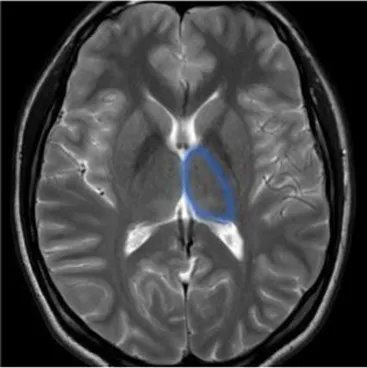

Most of the knowledge on neurodegenerative processes associated with stroke is based on studies with neuroimaging and in particular brain MRI, providing an excellent anatomical detail and gray/white matter contrast. For this reason, structural MRI, using conventional sequences, especially T1, T2-weighted, in addition to contrast enhancement, has become the accepted standard for routine examination of the brain, offering high sensitivity to anatomical location and morphological characteristics of pathological processes.

Studying the SNDG with conventional MRI, disruption to global functional connectivity has been revealed in the ipsi-lesional corticospinal tract and in the inter-hemispheric connections (corpus callosum), in the bilateral inferior fronto-occipital fasciculus and in the bilateral superior longitudinal fasciculus (34–36), in the ipsilateral thalamus, in the substantia nigra, hippocampus and in amygdala (37–39).